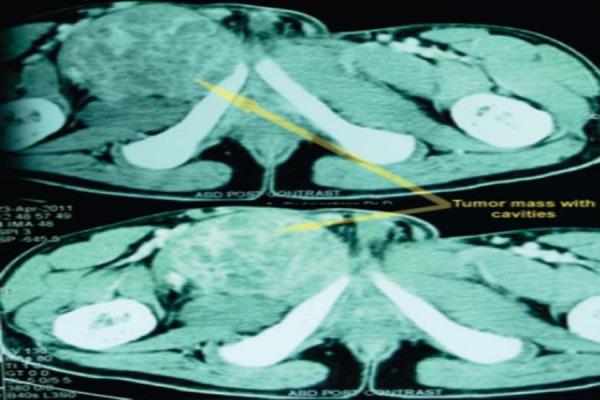

We present a case of a 21 year old male who presented with a swelling of the right inguinal region which was gradually progressive. Radiologically, there was a lytic expansile lesion of the superior pubic ramus. A contrast computed tomography revealed multiloculated cystic cavities and histopathology confirmed the diagnosis of ABC. Surgical excision of the complete tumor by anterior approach was done. Till date (2 years since surgery) patient has no recurrence.

我们报告一例21岁男性患者,其右腹股沟区出现逐渐增大的肿胀。影像学检查显示耻骨上支有溶骨性膨胀性病变。增强计算机断层扫描显示多房性囊腔,组织病理学确诊为动脉瘤样骨囊肿。通过前路完整切除肿瘤。截至目前(手术后2年),患者无复发。